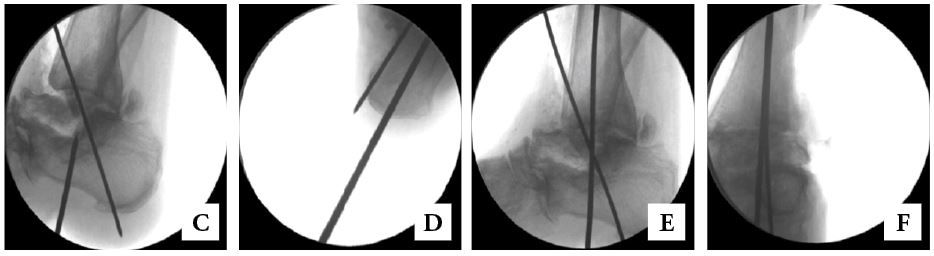

• Insert the guidewire under fluoroscopic guidance from plantar aspect across calcaneus, talus and distal tibia medullary canal (Figs. 7-A through 7-F).